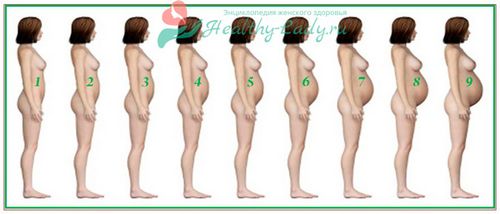

Багато вагітні знають, що ближче до терміну виношування живіт опускається, але не всі мають поняття як саме це виглядає. Тому починаючи з 32-34 тижнів все частіше придивляються до свого живота, намагаючись визначити, чи відбулися з ним зміни.

При нормальній вагітності, коли відсутні будь-які відхилення і патології, живіт у первісток починає змінюватися на 36 тижні. Якщо до цього він на вигляд нагадував велику кулю, щільно притискається до грудей, то після, його форма буде нагадувати загострений в області пупка овал (дивіться на фото нижче).

Як виглядає опущення?

Крім того, живіт змінюється за формою, якщо раніше він був круглим до 37 тижня приблизно, то після 38 його форма буде нагадувати грушу або загострений овал, що найчастіше видно неозброєним оком. Багатьом вагітним при цьому здається, що живіт став меншим обсягом, але це не так, він просто змінив форму.